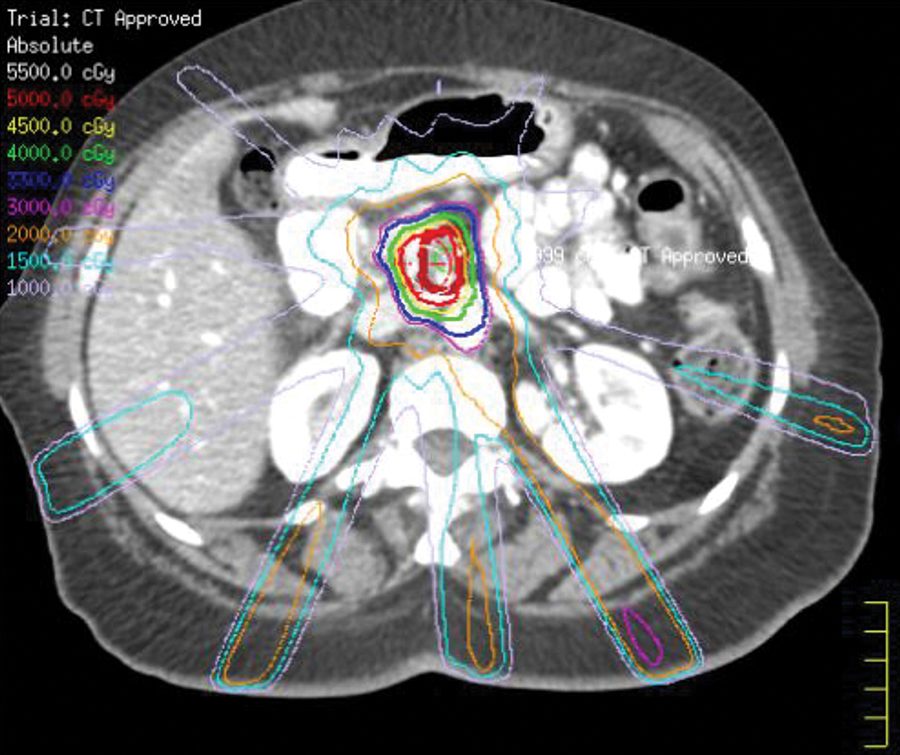

El ensayo PRO-ACTIVE está abierto a los pacientes que recibirán radioterapia en ambos lados del cuello, con una dosis total de al menos 60 Gy durante más de 6-7 semanas. Se excluyen los pacientes con disfagia en el momento de la inscripción. Al inscribirse, cada paciente es asignado aleatoriamente al grupo de tratamiento reactivo, proactivo de baja intensidad o proactivo de alta intensidad.